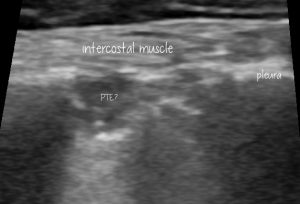

Finally, I want to talk about pulmonary thromboembolism (PTE): a subject not much addressed in small animal sonography texts.

Other cases I’ve seen with putative PTE have had irregular subpleural consolidations. These are usually quite small, often wedge-shaped and lack the surrounding B lines characteristic of acute pneumonias.

The following patient was a dog with PLE-induced hypoalbuminaemia, a large RV thrombus and acute tachypnoea.

Some better, still images of those lung lesions: